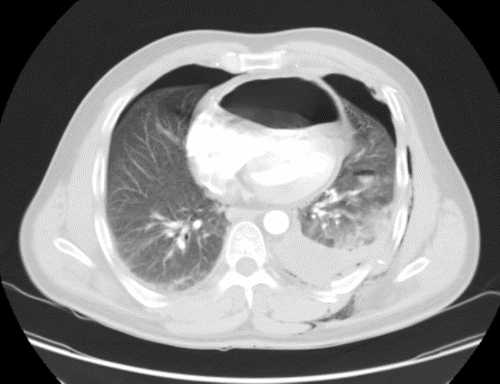

The patient's condition stabilized, and the pain was controlled with analgesia. CT showed no brain injury, but there were multiple left-sided comminuted rib fractures with displacement along the posterior and lateral aspects. In addition, it revealed the presence of hydropneumothorax; lung contusion with thoracic wall subcutaneous emphysema; right-sided mild pneumothorax; undisplaced fracture of the sternal body; herniation of the stomach into the pericardial cavity (Figure 1); no intraabdominal fluid or air and no solid organs injury; fracture of the transverse processes of the L3/L4 and L5 vertebrae; fractures of the left glenoid bone and left pelvic bone; multiple comminuted displaced fractures involving the iliac, acetabular, and pubic bones, with the displacement of the iliac bone fractures; right inferior pubic ramus nondisplaced fractures; and fracture of the left sacral alar and proximal left sacral segments (Figure 2).

Figure 1. CT of Herniated Stomach into Pericardial Space. A) Scout, (B) Axial, (C) Sagittal, and (D) Coronal Views. Published with Permission

B) Axial View

The diagnosis of pericardial rupture, similar to classic diaphragmatic injury, is not easily made and mainly depends on heightened awareness. However, in cases of severe trauma with a large diaphragmatic defect, intra-abdominal organ herniation develops immediately, with significant clinical and radiological findings, which facilitate early diagnosis and proper immediate management,1 similar to our case. CT is a valuable imaging modality with a sensitivity and specificity of 54%-73% and 86%-90%, respectively.1 In addition, it is the gold standard for diagnosing pericardial hernia as it reveals the herniation of abdominal organs into the pericardial space.2 In our case, contrast-enhanced, full-body trauma CT was performed, which revealed intrapericardial gastric herniation causing restriction of the pericardial cavity and displacement of the heart. Moreover, it was sufficient to confirm the diagnosis of a pericardial hernia.